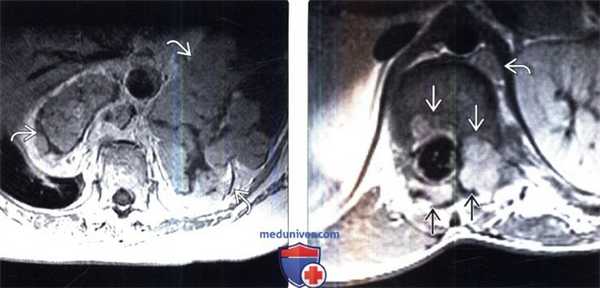

(Слева) Аксиальный срез, Т1-ВИ с КУ: крупная неравномерно-дольчатая ЗООПН забрюшииного пространства, характеризующаяся неоднородным контрастным усилением сигнала.

(Справа) Аксиальный срез, Т1-ВИ с КУ нижнегрудного отдела позвоночника: накапливающее контраст объемное образование в просвете левого неврального отверстия, деформирующее тело и задние элементы позвонка. Позади ножки диафрагмы слева также видна накапливающая контраст нейрофиброма.